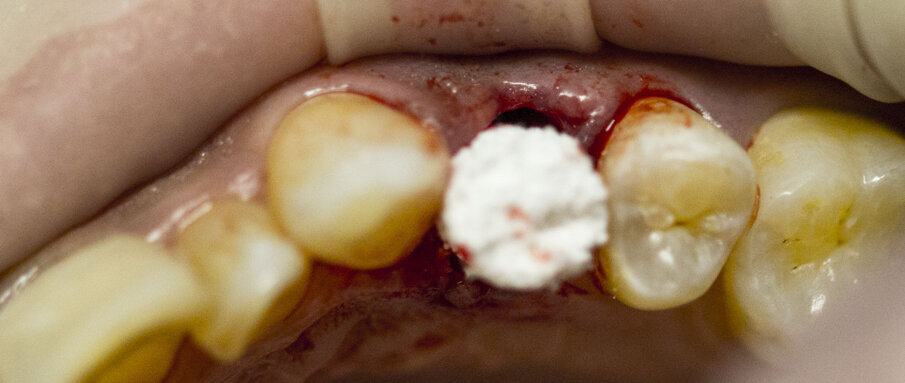

Oltre all’ovvia necessità di un’adeguata sutura del lembo, è risaputo che l’inserimento di spugne di collagene di tipo I riduce al minimo il rischio di complicanze controllando il sanguinamento, proteggendo la ferita e stabilizzando il coagulo. Il suo riassorbimento avviene normalmente in 10-14 giorni attraverso l’azione di collagenasi e peptidasi. Spugne o altri materiali devono essere posizionati attentamente per evitare una compressione eccessiva, che potrebbe causare ischemia e causare un problema nella rivascolarizzazione (Figg. 12-14).

Fig.12 - Gli elementi 3.3 e 3.4 devono essere estratti.

Fig. 13 - Avulsione di 3.3 e 3.4.

Fig. 14 - Spugne emostatiche (Hemocollagene, Septodont) sono state inserite nei siti di estrazione.